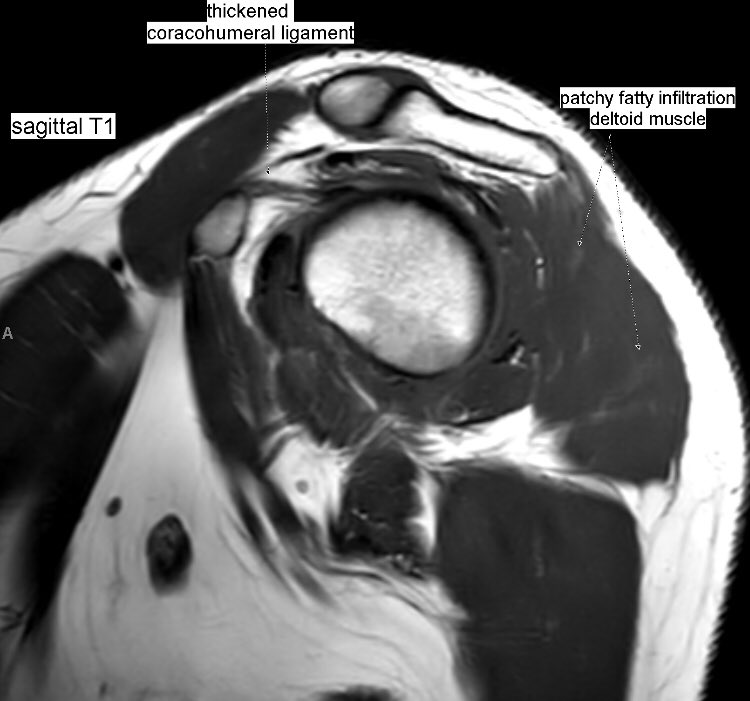

Edema + patchy fatty infiltration of supraspinatus, infraspinatus, deltoid and teres minor muscles. Parsonage-Turner syndrome (acute brachial plexus neuritis) of suprascapular + axillary nerves. Associated adhesive capsulitis.

#MSKrad#shoulder#orthotwitterpic.twitter.com/1C0f9g30Ad